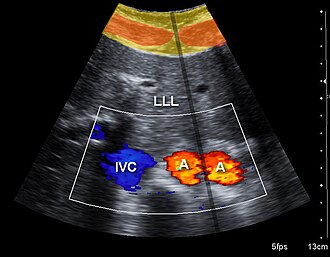

Ultrasonografija ili ehosonografija (lat. sonus: glas, zvuk) je upotreba ultrazvuka u dijagnostičke svrhe. Izvor ultrazvuka prisloni se na tijelo, a reflektirani signali ultrazvučnih valova prikazuju se na zaslonu osciloskopa. Na osnovi različite akustične gustoće mogu se prikazati različne strukture (tkiva, organi) u tijelu. Dvodimenzionalni sustav na Dopplerovu učinku (takozvani kolor dopler) omogućuje procjenu protoka krvi u žilama određenog područja. Ehosonografija je našla obilnu i korisnu primjenu u ginekologiji, porodništvu (praćenje razvoja čeda u maternici, rano otkrivanje nepravilnosti), u kardiologiji (ehokardiografija), neurologiji (ehoencefalografija), oftalmologiji (ehooftalmografija) i drugdje. [1]

Ehokardiografija je skupina neinvazivnih pretraga srca ultrazvukom. Temelji se na registraciji ultrazvučnih valova što ih reflektiraju srčane strukture. Ehokardiografija je dominantna metoda kardiološkog pregleda koja, pouzdanim podatcima, najčešće otklanja potrebu za invazivnim pretragama srca. Daje ključne podatke za dijagnozu: funkcijske parametre, točne mjere srčanih šupljina i debljine stijenki, oblik srčanih struktura, vrijednosti intrakardijalnih tlakova, procjenu težine bolesti srčanih zalistaka i drugo. Jednodimenzijska ehokardiografija (M-prikaz, od eng. motion: kretanje) prikazuje gibanje srčanih struktura s pomoću jednoga piezoelektričnoga kristala i daje najbolji vremenski prikaz zbivanja u srcu. Dvodimenzijska ehokardiografija daje slojevne slike srčanih struktura u "živoj slici" s dobrom prostornom orijentacijom. Dopplerova ehokardiografija primjenjuje se osobito u dijagnostici prirođenih i stečenih bolesti srca. [2]